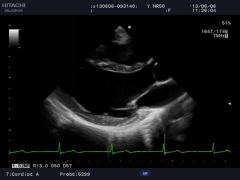

臨床圖例

TDI組織多普勒成像

TDI已成為重要的心臟功能評估技術(shù),能夠精確分析高幅、低頻多譜勒頻移及通過彩色編碼實時顯示心肌組織的運動速度。TDI能夠無創(chuàng)診斷心肌收縮、舒張的速度,進行左室收縮、舒張功能的評價,特別在舒張功能的評價方面,TDI能夠在收縮功能受累之前的心肌運動低下的病人得到早期的診斷,并得出沿室壁內(nèi)膜運動的速度,用以評價左室節(jié)段運動的狀態(tài),獲得高質(zhì)量的多譜勒信息,測出速度、平均速度和瞬間加速度等參數(shù)值。此項技術(shù)為臨床冠心病、心肌病、心律失常等多種疾病的診斷提供了可靠的診斷依據(jù)。